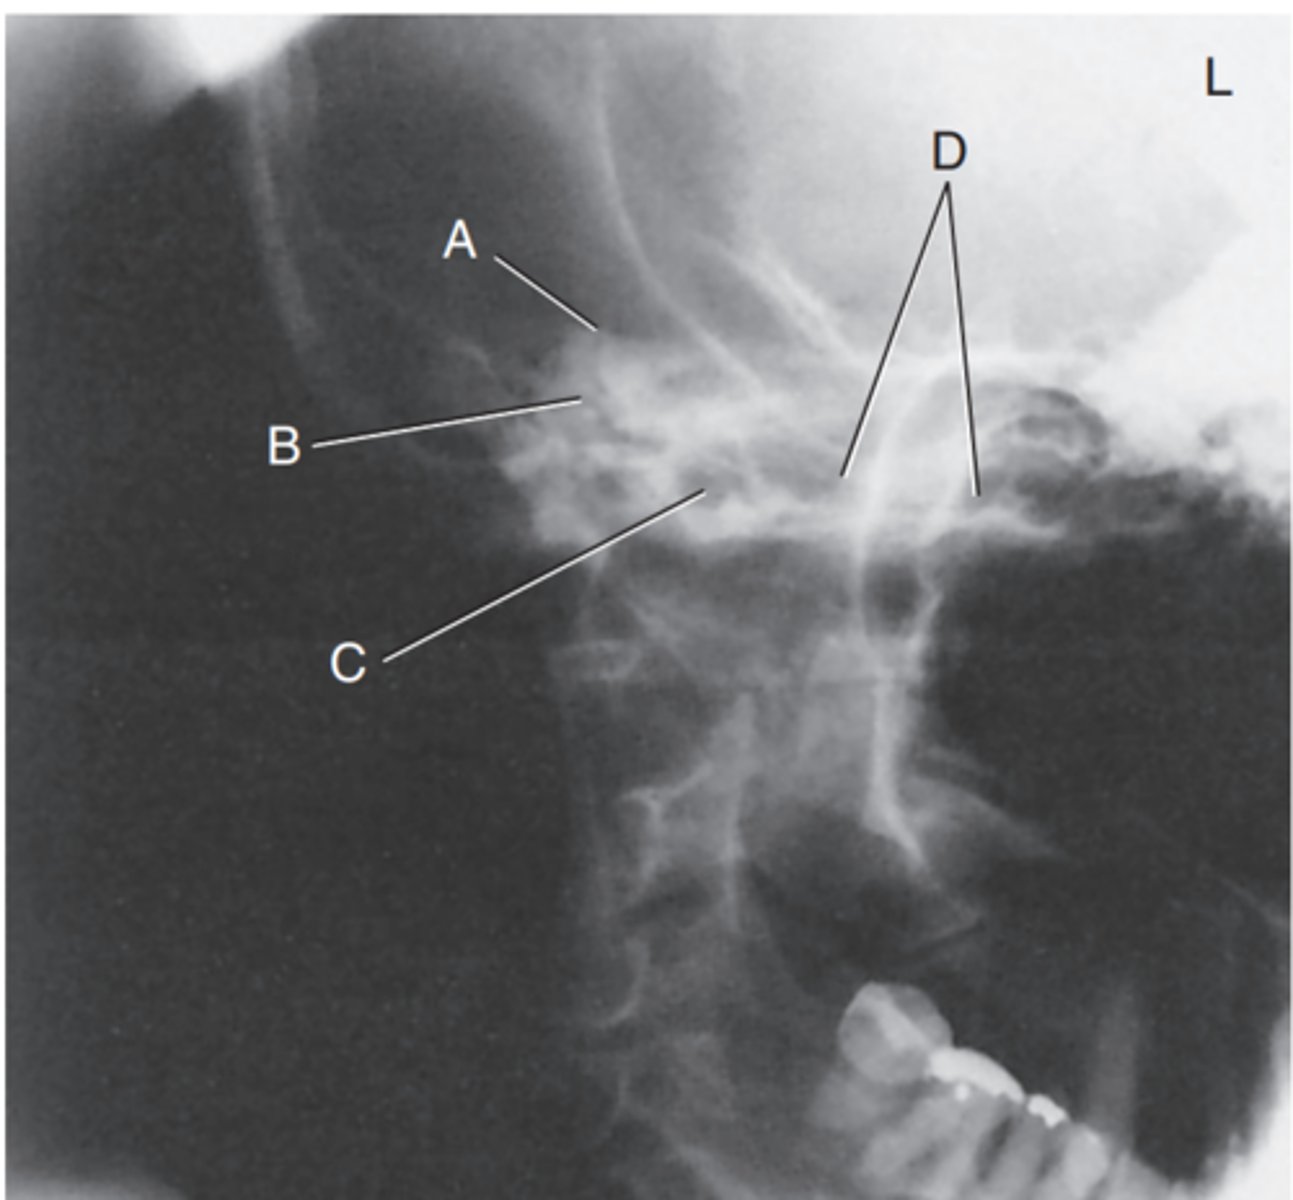

Label A

Mastoid antrum

Label B

Mastoid air cells

Label C

Downside mandibular condyle (just anterior to EAM)

Label D

Upside (magnified) mandibular condyle

Label E